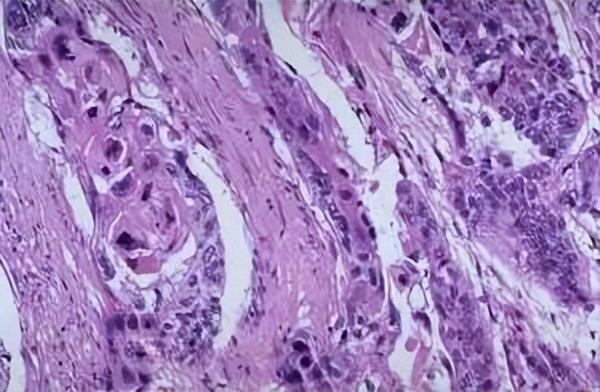

4.甲鳞状细胞癌

是最常见的甲恶性肿瘤,最常发生于指甲,位于甲床内或侧甲沟内。甲鳞状细胞癌通常发生于年岁 较大的男性。现在 医学界以为 的可能引发甲鳞癌发作的因素有创伤、辐射袒露、吸烟及人乳头瘤病毒16、18型熏染。

也正是由于 甲周及甲下鳞癌的临床特征很一样平常 ,无特异性,因此,经常不能早期确诊,使诊断恒久延迟。

甲的一些体现,如角化太过、一连 性甲剥离、纵向红甲、疣状增生、甲沟炎、甲板营养不良或甲下肿块,看起来都很无害,无法引起患者及医生的重视,可是 若一连 存在疣状或角化性病变,或者经寻常疣冷冻治疗或其他治疗后复发,应引起嫌疑 ,尽早举行 活检检查。治疗方案也是依据肿瘤的分期接纳差异规模的切除。